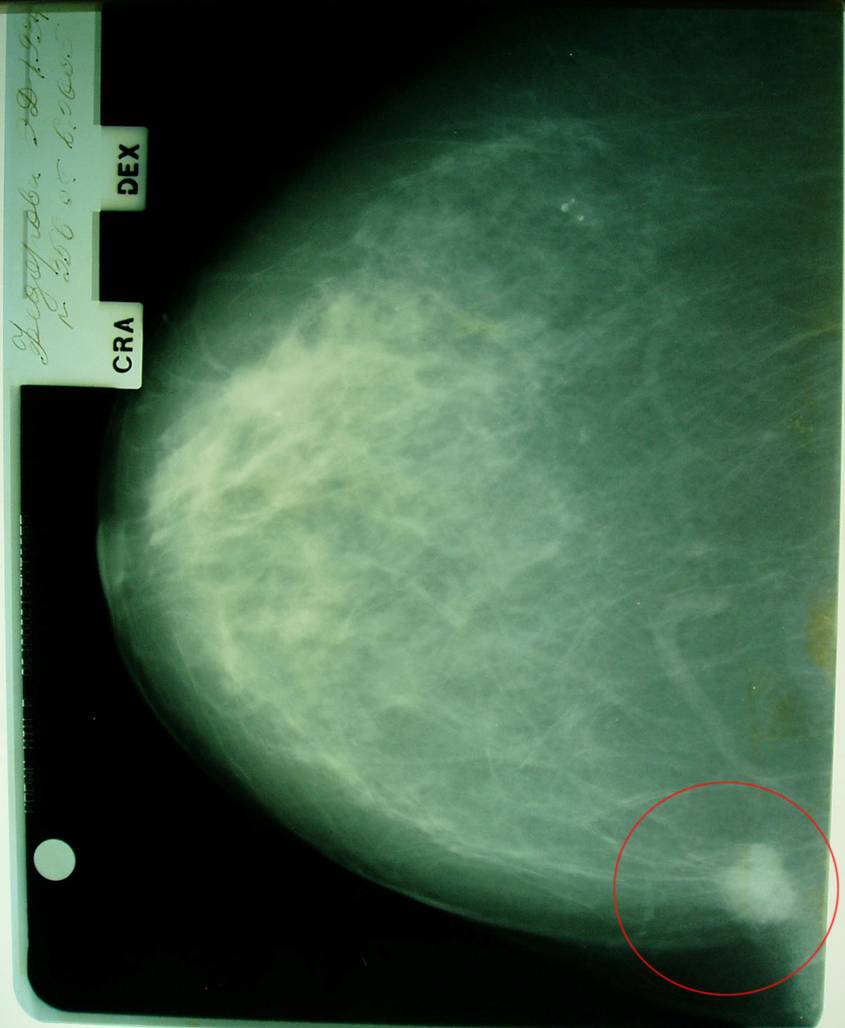

Маммограмма в динамике.

Больная раком правой молочной железы T4аN0M0. Регресс.

12.09.2005 (после лучевой терапии)